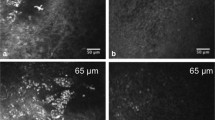

Corneal imaging in health and dry eye disease. a Horizontal OCT section of the normal human cornea showing the epithelium, Bowman’s membrane, stroma, Descemet’s membrane and endothelium. In vivo confocal micrographs (IVCM) of the cornea in normal and dry eye subjects (b–g). b Normal superficial epithelium showing regularly arranged cells with dark nuclei. c Superficial epithelium in dry eye disease showing squamous metaplasia, hyperreflectivity, and lower cell density as compared to normal. d Subbasal layer showing normal corneal nerve plexus and dendritic cells. e Subbasal layer in dry eye with increased density of dendritic cells. f Reduced density of nerves. g Hyperreflective and tortuous nerves. IVCM image: magnification: ×800

Cornea

In vivo confocal microscopy is emerging as a promising tool in the study of corneal ultrastructure, both in health and disease. The ability of IVCM to examine each layer of the cornea in detail and to identify pathological changes at the cellular level is particularly useful in DED, where the changes are often subclinical and are not picked up by the standard slit-lamp biomicroscopy. IVCM provides high-resolution images of the individual layers of the cornea, i.e., the epithelium, Bowman’s layer, stroma, Descemet’s membrane and the endothelium. Further, the subbasal corneal nerve plexus, stromal nerves [159–162], and dendritiform and non-dendritic immune cells can be clearly identified.

The outermost corneal layer, the epithelium consists of the superficial epithelial layer, an intermediate and the innermost basal cell layer. Being an ocular surface disease, DED affects the superficial epithelial cells. IVCM reveals reduced density and morphological alterations of superficial epithelial cells [163–168]. These corneal superficial epithelial cells increase in size, and cell borders become hyperreflective and irregular. Further, the nuclei become prominent and hyperreflective, and increase in size [163]. These changes are attributed to desquamation and squamous metaplasia. Erdelyi et al. also reported a decrease in the intermediate cell layer [165]. Moreover, increased epithelial basal cell density has been reported in a number of studies [164–166], which has been postulated to be due to the fact that there is an increased turnover of epithelial cells as a result of the epitheliopathy.

Epithelial dendritic cells are the major type of immune antigen-presenting cells in the cornea, and are responsible for generating an immune response or maintaining tolerance [169, 170]. These dendritic cells are primarily located in the subbasal layer in close proximity to the subbasal nerve plexus, with their density declining from the periphery towards the center [170–172]. Using confocal microscopy, Lin et al. have shown an increased number of dendritic cells in DED, both in the center and the periphery [173]. They also suggest that that the numbers of dendrites represent an active stage of these cells. Similarly, Tuisko et al. showed an increased infiltration of the subbasal nerve plexus with purportedly mature antigen-presenting cells [171]. A similar increase in central corneal dendritic cells has also been reported in conditions such as infectious keratitis, with the area covered by these cells (cell field) and their number of dendrites demonstrating the mature and active stage of these cells [174]. Finally, an increase in the number of non-dendritic leukocytes has also been noted in the cornea in DED [173, 174]. Both quantitative and qualitative changes in the nerve plexus have been reported in DED. Examination of the corneal nerve morphology using IVCM has shown various abnormalities such as increased tortuosity, reflectivity, and beading [164, 166, 175, 176]. These morphological changes are believed to be due to the damage and subsequent attempted regeneration of subbasal nerves. Different studies have demonstrated somewhat conflicting results with regard to nerve density. Benitez et al. and Villani et al. in 2007 have reported a decrease in the density of the nerves [164, 175, 177] and this reduction in density is in concordance with decreased clinical corneal sensitivity [164, 171, 175, 177–179]. However, some studies have shown no change or even an increase in the nerve density [163, 176, 180], and hypersensitivity of the cornea has been reported clinically [171, 181]. These changes may be explained by the fact that different stages and severity of DED induce different degeneration/regeneration patterns of nerves.